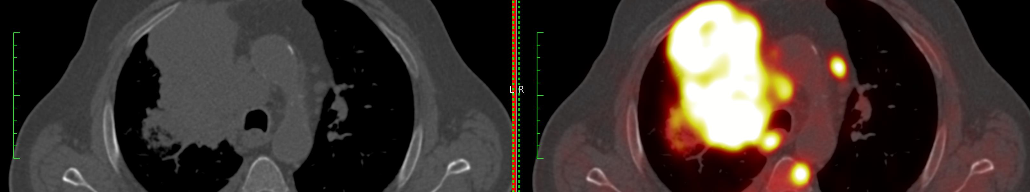

Заблаговременно диагностировать хроническую болезнь почек возможно при помощи совмещенной позитронно-эмиссионной и компьютерной томографии (ПЭТ/КТ), считают ученые Тюменского государственного медицинского университета Минздрава России (ТМУ) – сообщают РИА Новости1. Результаты исследований опубликованы в журнале "Урология".

"ПЭТ/КТ – это высокотехнологичная визуализация углеводного и липидного метаболизма в различных органах, в результате видна молекулярно-клеточная жизнеспособность тканей в режиме реального времени. Раньше этот метод применяли только в онкодиагностике. Мы выяснили, что с его помощью можно зафиксировать поражение почек на ранней стадии. Пациенту вводятся меченые молекулы глюкозы, наблюдая за их фиксацией клеточными структурами почек, можно увидеть и рассчитать жизнеспособность органа, а также отследить регионы уменьшения метаболической активности", – рассказал профессор кафедры хирургии и урологии с курсом эндоскопии ТМУ Борис Бердичевский.

Опухоль "любит" глюкозу и загорается ярким светом на экране врача-радиолога, объяснил специалист. Вместе с тем и обычные органы не могут обеспечивать нормальную жизнеспособность человеческого тела без глюкозы. Раньше врачи не обращали внимания на разницу между ее захватом здоровыми клетками и теми, которые уже склонны к поражению. Вторые находятся на стадии "оглушения ткани", если на этом этапе не выявить проблему, то орган медленно гибнет.

"Клетка снижает потребление глюкозы при начале любой болезни, влияющей на ткани, у нее как бы падает “аппетит”. Когда количество поглощаемого углевода снижается на 10 процентов, то явной опасности нет, если же показатель превысит 30 процентов, значит, клетки уже “оглушены” и пора подбирать соответствующую терапию", – продолжил профессор Бердичевский.